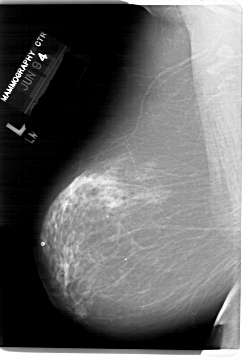

A_1503_1.LEFT_MLO

LEFT_MLO LINES 6871 PIXELS_PER_LINE 4606 BITS_PER_PIXEL 12 RESOLUTION 43.5 NON_OVERLAY